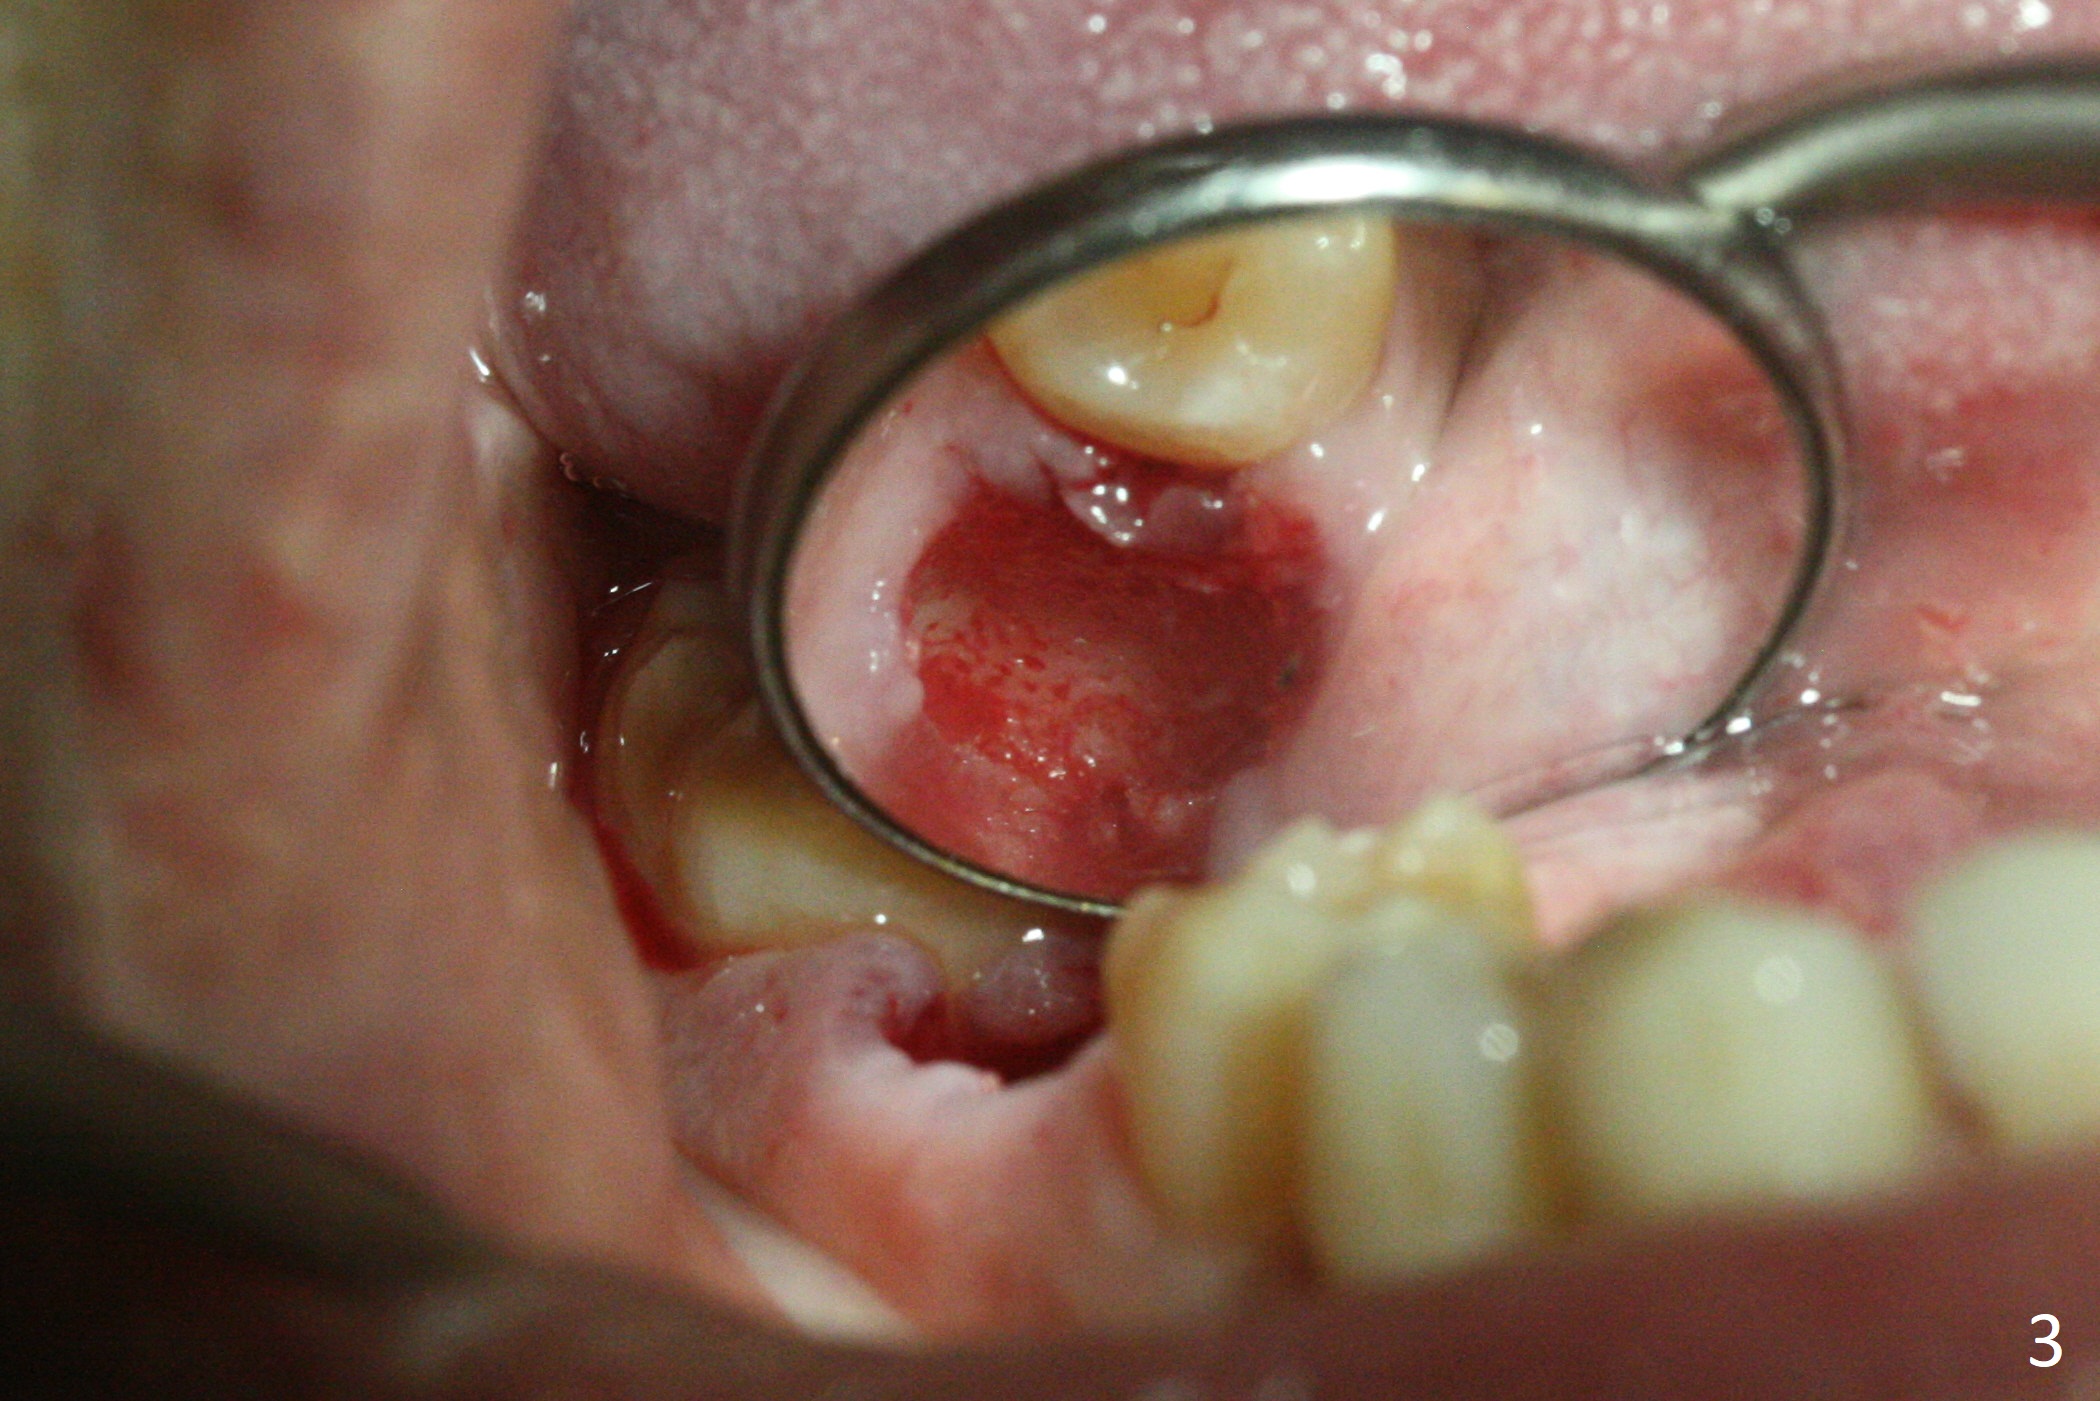

After removal of the residual roots at #30 (Fig.1), a thin septum (Fig.2 *) is removed with Rongeur (Fig.3). Following use of 4.8 mm Magic Drill, a 5x9 mm dummy implant is placed (Fig.4). To reduce socket gap (*), a 6 mm IBS implant is inserted with >50 Ncm (Fig.5). What is unexpected is heavy reduction in the height of a 6.5x4(3) mm abutment (A) because of the short crown height of the lower posterior teeth (Fig.1) and supraeruption of the tooth #3. The immediate provisional is unstable postop. The remade one dislodges soon, so does the abutment (Fig.6, 3 months postop). It appears that bone pattern in the distal socket changes.